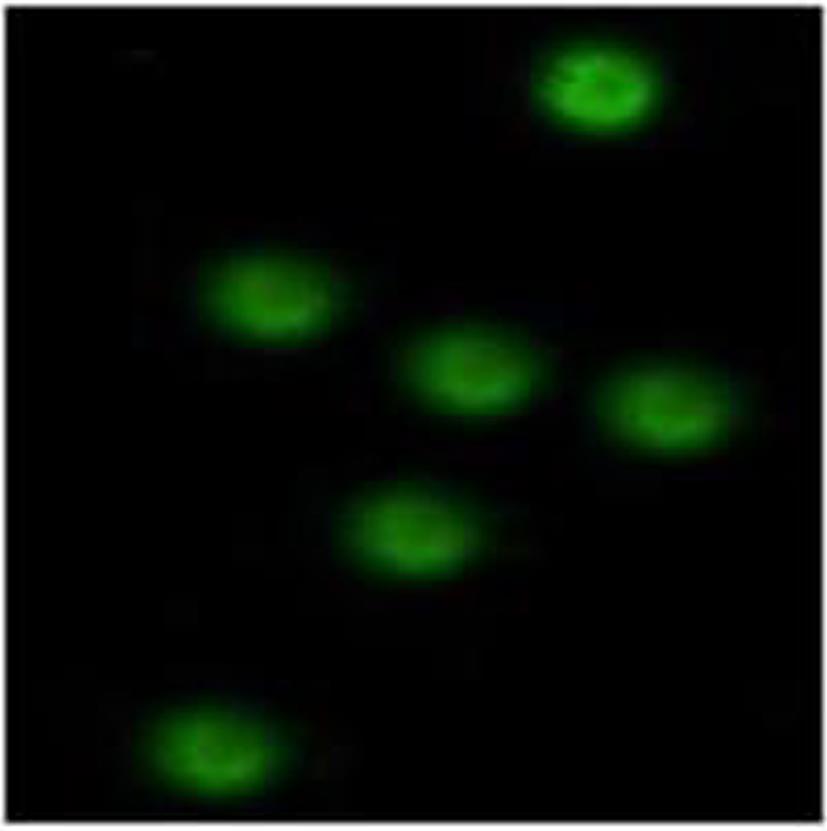

Niemann-Pick disease type B and heterogeneous manifestations of its liver involvement: A case report

Qiao YANG, Yi SHEN, Yue SHI, Jin WANG, Fangfang LYU

2024, 40(2): 356-360. DOI: 10.12449/JCH240221

Abstract(977) HTML (336) PDF (1123KB)(101)

Abstract:

This article reports a case with the chief complaint of “hepatosplenomegaly to be investigated” and a confirmed diagnosis of Niemann-Pick disease type B after various tests, and a literature review was conducted to summarize the heterogeneous manifestations of liver involvement in type B Niemann-Pick disease, in order to improve the clinical management of difficult and rare liver diseases.